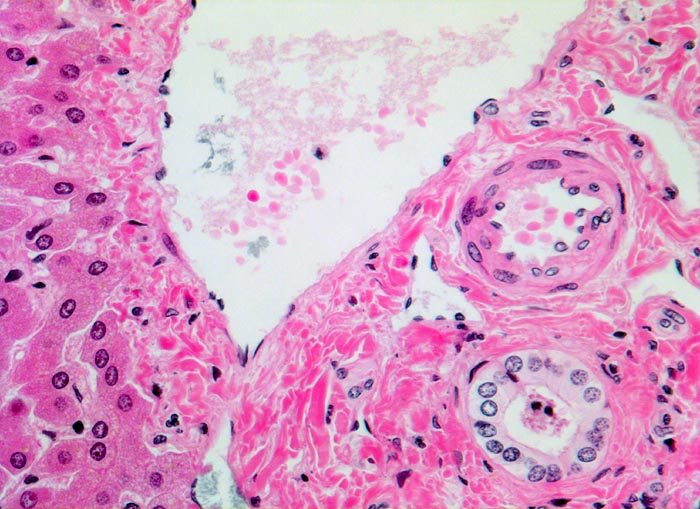

Bei ausgeprägten Eisenablagerungen zeigen parenchymatöse Organe eine Braunverfärbung (> 1521). Die Bestimmung des histologischen hepatischen Eisenindexes nach Deugnier erlaubt eine Abgrenzung der genetisch bedingten Hämochromatose von einer Hämosiderose. Dabei werden Verteilung und Ausmass der Eisenablagerungen berücksichtigt. Bei der Hämochromatose wird das Eisen primär in den periportalen Hepatozyten abgelagert, später auch in Gallengangsepithelien und Gefässendothelien. Bei nicht genetisch bedingter Hämosiderose finden sich die Ablagerungen vor allem in Kupffer Zellen (> 00975).

• Diffuse grobgranuläre Eisenpigmentablagerungen im Zytoplasma von Hepatozyten, Gallengangsepithel und Gefässendothel der Gefässe in den Portalfeldern.

• Gruppen von stark eisenbeladenen Kupffer'schen Sternzellen. Das sollte der Kliniker dem Pathologen mitteilen: